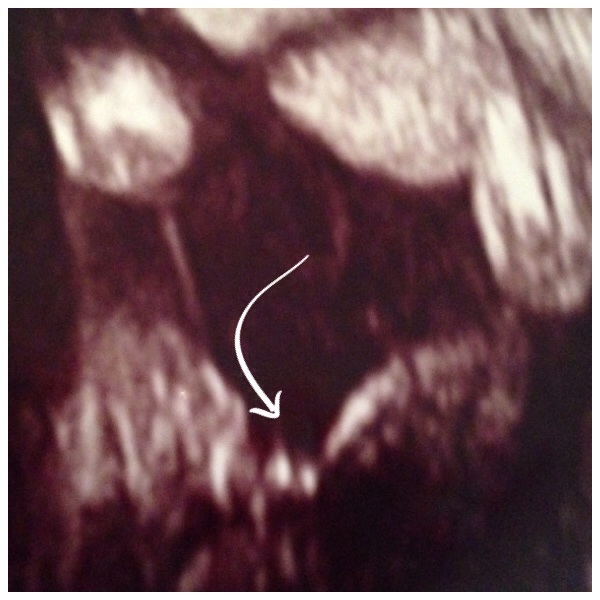

I have a photo if my 3 pregnancies

My two boys at bottom this #3 pregnancy top

(The head shape looks more rounded)

Attachment 14571